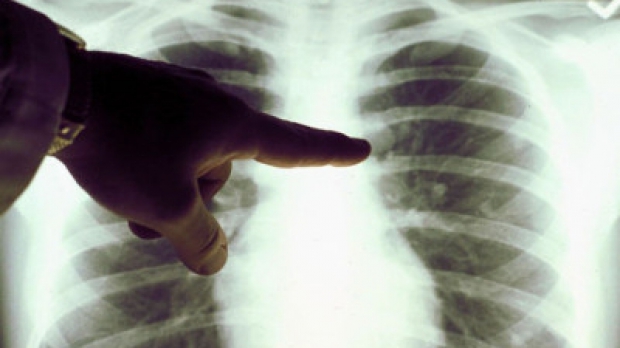

De asemenea, este foarte important ca pacientul să rămână internat pe toată perioada de contagiozitate a bolii. TBC este a doua cauză infecţioasă de deces în lume, doar SIDA făcând mai multe victime. Se estimează că o treime din populaţia lumii este infectată cu bacilul Koch, iar la circa 5 – 10% dintre aceştia, infecţia latentă progresează într-o formă de boală activă. Trebuie subliniat faptul că în 80% din cazurile de TBC, procesul tuberculos se localizează la plămâni.